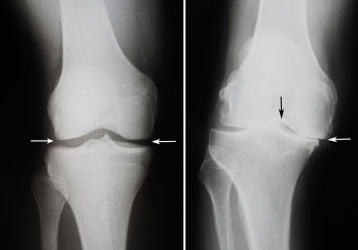

Народные средства лечение деформирующего артроза коленного сустава

Народные средства лечение деформирующего артроза коленного сустава. Рецепты приготовления мазей, компрессов, растворов и другие советы.